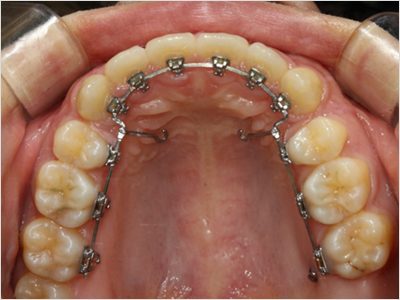

LINGUAL ORTHODONTICS

설측교정은 치아 안쪽(설측면)에 초소형 장치로 보이지 않게

아름다운 미소를 만드는 고난이도 프리미엄 교정 치료입니다.

난이도가 높은 만큼 풍부한 진료 경험이 중요합니다.

강남에서 다년간 설측교정에 특화된 경험을 바탕으로,

3D 디지털 기술을 활용한 맞춤 설계, IDBS방식을 통한

정밀하고 불편감 없는 치료를 제공합니다.

설측교정

상악

교정장치를 안쪽에 부착

하악